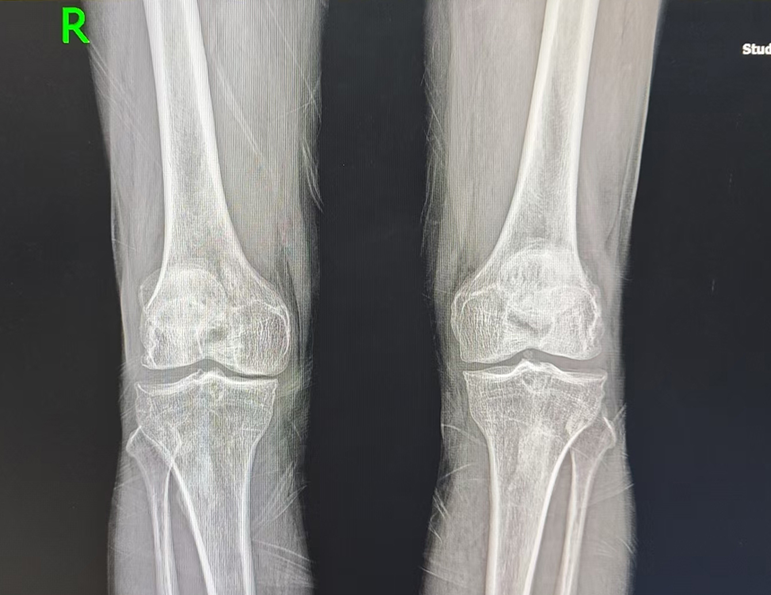

今年64岁的田大爷家住山东淄博,平日里身体还算硬朗,曾几何时,走几里地对他而言并非难事。可随着膝关节炎病情逐年加重,行走渐渐变成了一种奢望。“以前膝盖只是偶尔疼,还能勉强控制,从去年开始,疼痛越来越厉害,走不了多远就疼的受不了。”深受病痛困扰的田大爷,为了改善晚年生活质量,下定决心接受手术治疗。

在亲戚的推荐下,田大爷慕名来到济南关节外科医院。入院后,医护团队为田大爷进行了全面、细致的检查,明确其符合膝关节置换手术指征。结合田大爷的年龄、身体状况及康复需求,医院手术团队反复研讨,为其定制了Mako智慧机器人辅助全膝关节置换的手术方案,并顺利完成手术。